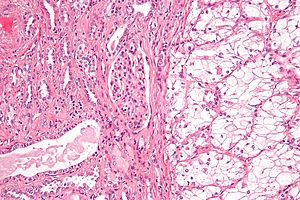

Clear cell renal cell carcinoma:

This is the most common form of renal cell carcinoma. About 7 out of 10 people with RCC have this kind of cancer. When seen under a microscope, the cells that make up clear cell RCC look very pale or clear.